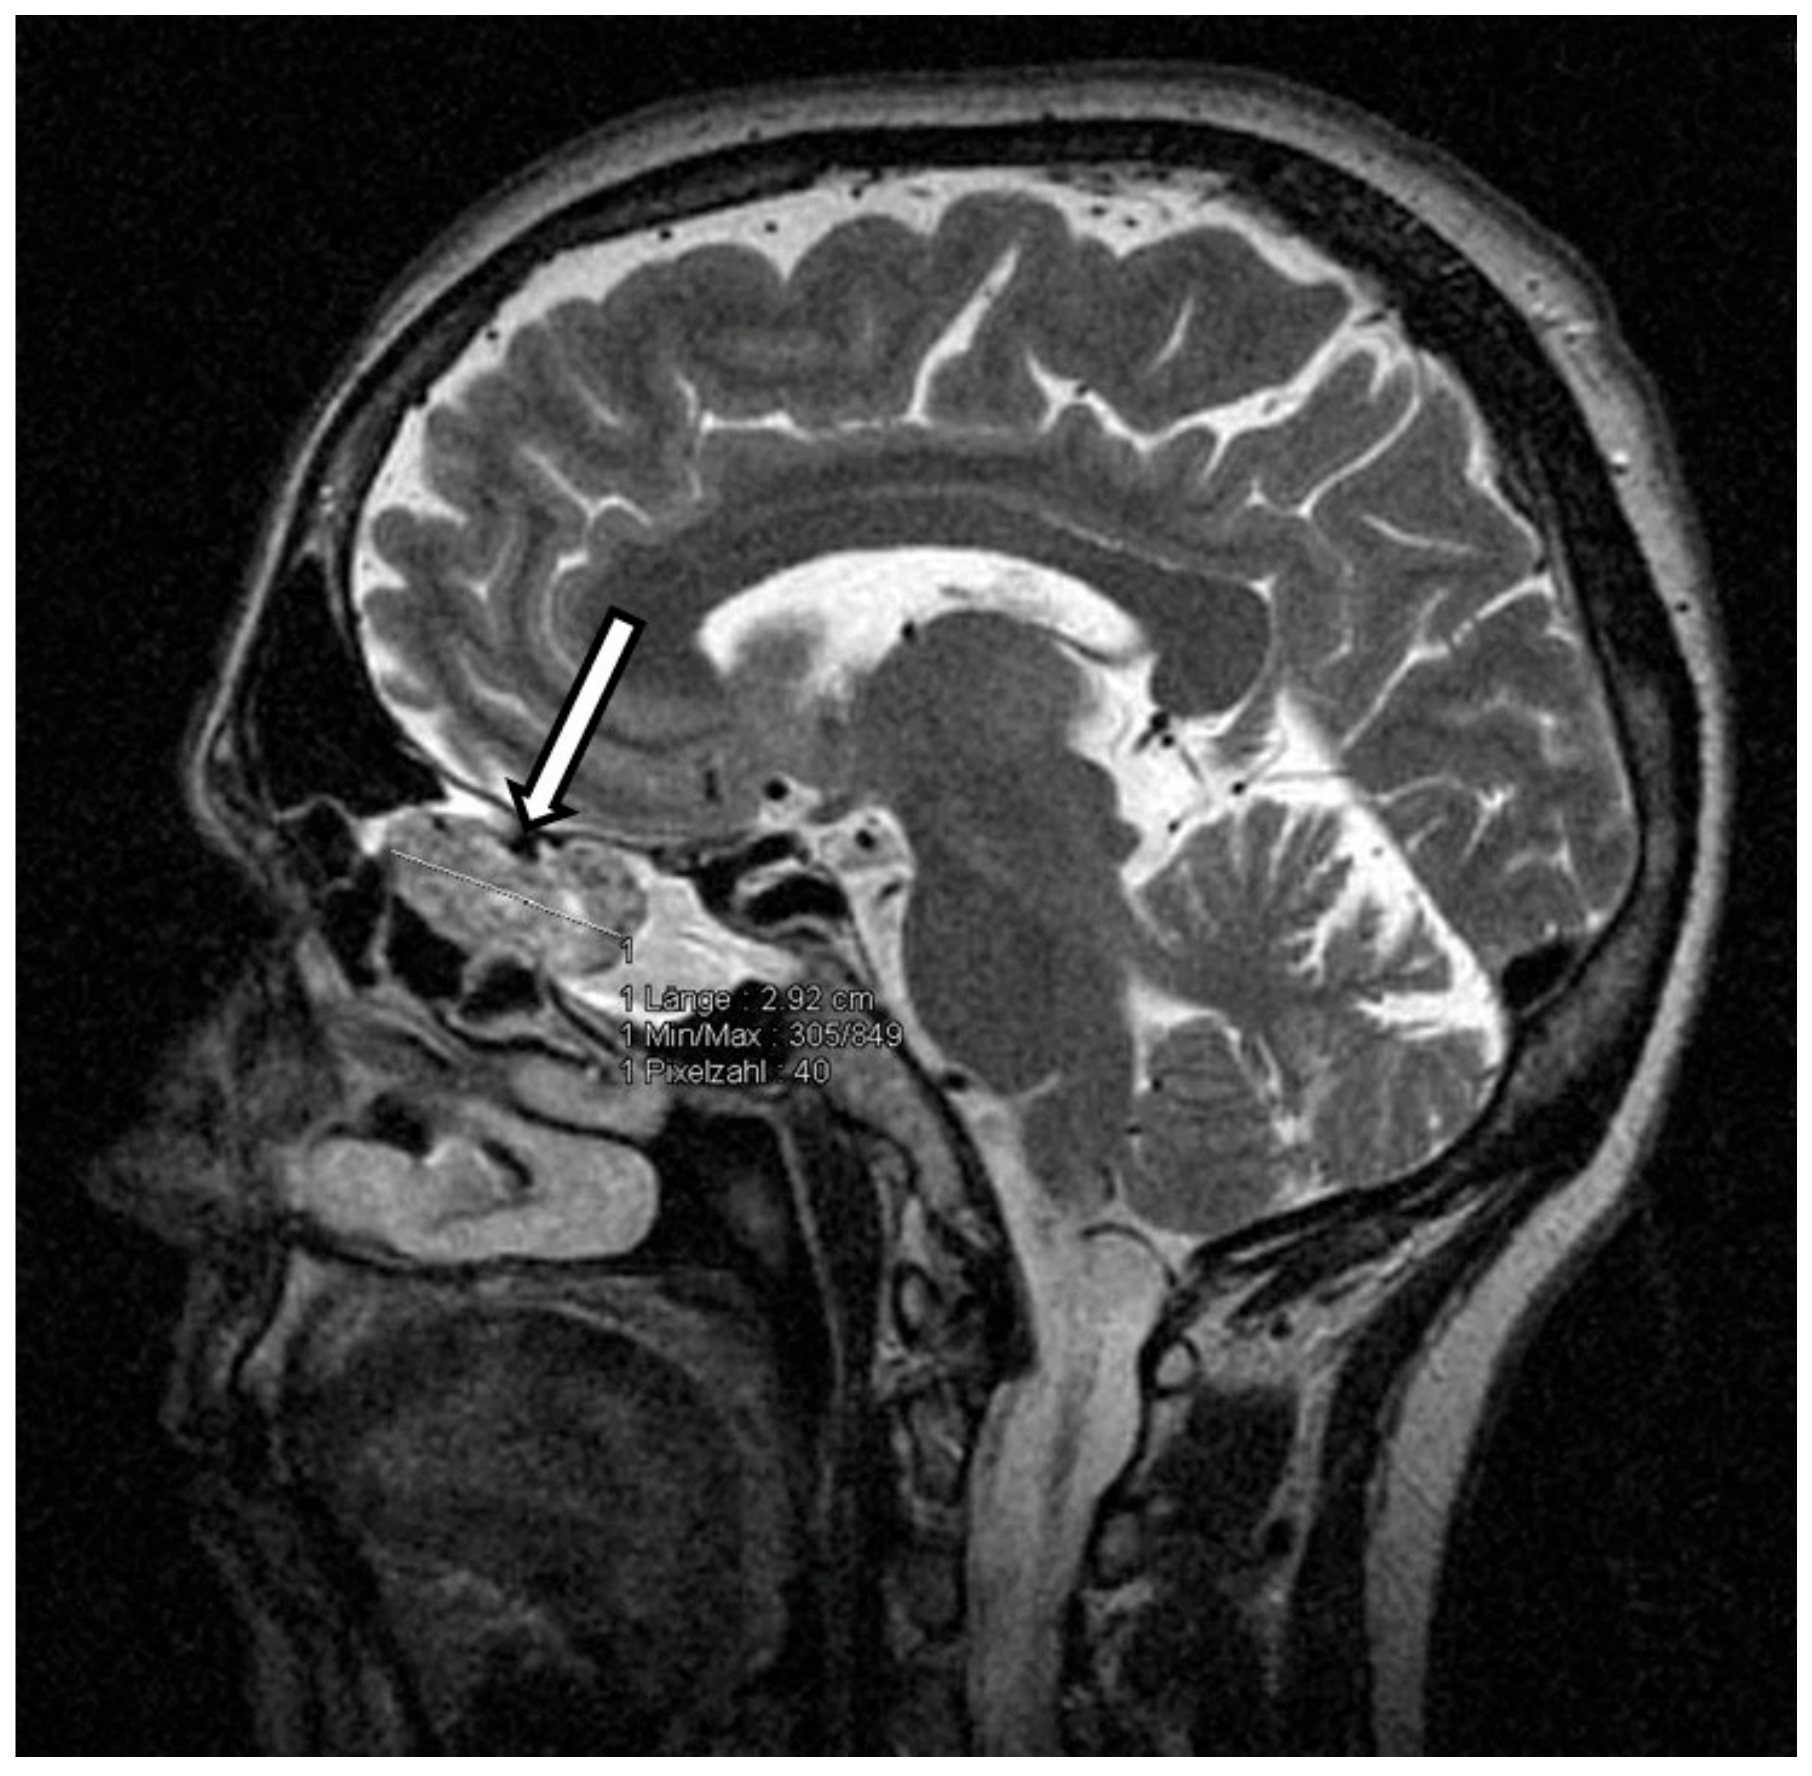

Thus, oncogenic osteomalacia due to neoplastic FGF-23 secretion was suspected. FDG-PET-CT and subsequently DOTATATE-PET-CT imaging demonstrated no tumor. Since the cranium was not represented in both PET-CT scans, contrast enhanced cranial MRI was performed and finally revealed a tumorous mass in the left cellulae ethmoidales with an expansion of 3.2 cm × 1.4 cm × 1.8 cm and intensive contrast enhancement (Figure 1). Remarkably, retrospective analysis of an MRI scan of the head, which had been performed months earlier in an outpatient clinic, already showed the tumor, which had not been described back then. Even in retrospect, our patient denied symptoms possibly related to a tumor located in the cellulae ethmoidales, such as nasal obstruction, epistaxis, hyposmia, diplopia, tuba eustachii obstruction, or frontal headache.

Figure 1. MRT scan of the cranium. Arrow—tumorous mass in the left cellulae ethmoidales.